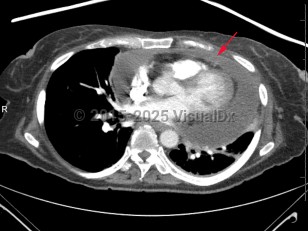

Imaging Studies image of Cardiac tamponade - imageId=7878229. Click to open in gallery.  caption: '<span>Axial CT image demonstrates a  large pericardial effusion which is flattening the cardiac ventricles  and concerning for tamponade.</span>'

Axial CT image demonstrates a large pericardial effusion which is flattening the cardiac ventricles and concerning for tamponade.